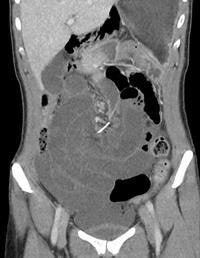

After an initial visit to the emergency department (ED) where she had been thought to have biliary colic, a previously healthy 30-year-old woman returned to the ED two days later complaining of worsening central abdominal pain, according to the group from Sir Charles Gairdner Hospital in Nedlands, Western Australia. A CT scan of the abdomen showed a metallic, wire-shaped foreign body at the mesenteric root of a small-bowel volvulus. The wire had pierced several parts of the small bowel, causing the volvulus.